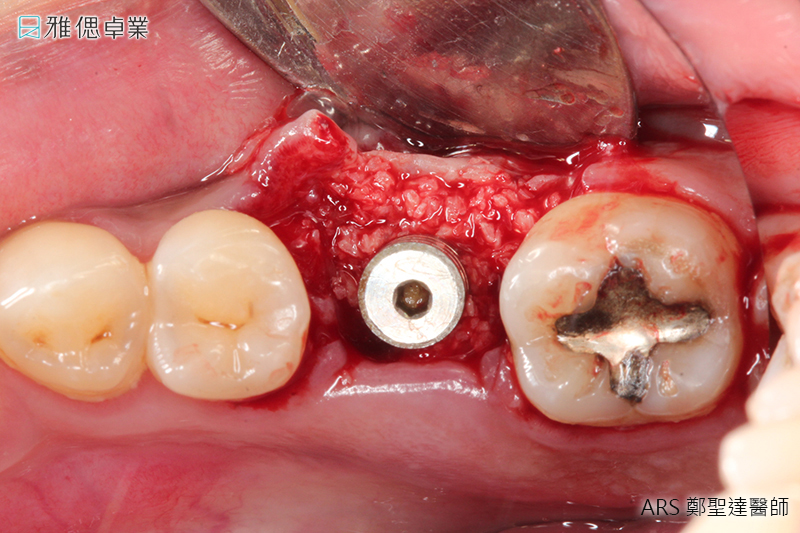

STEP2 植入人工植牙手術

局部麻醉後,醫師會利用手術導引板抓取精準位置與角度,將植體放入齒槽骨中,先進的數位導引板不僅能縮小手術誤差,同時也可控制傷口範圍,使植牙術後的癒合更為迅速。植入人工牙根後,骨細胞就開始進行植體的整合。

STEP3 牙齦塑形

植體在人體內3個月後,骨整合已經足夠支持咬合力,為了塑造未來牙套的牙齦型態,醫師會在植體上端接入牙齦成形帽,使牙齦生長為理想形狀。